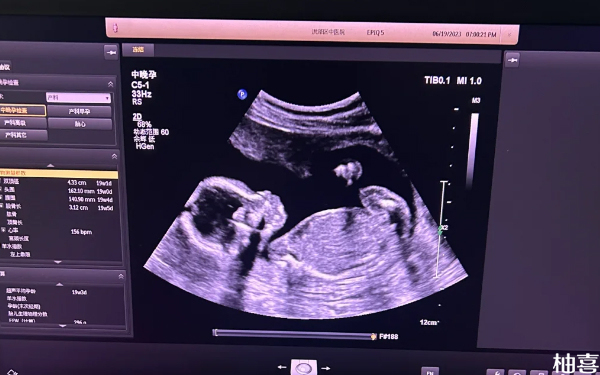

促排卵针打了后多久打夜针?

不孕不育症女性患者一般在使用促排卵药物8-12天后打夜针,夜针通常为肌肉注射或皮下注射药物,需要来诊用药;一般注射夜针后34-36小时后取卵。而在此期间,为保证卵泡的正常发育,建议在饮食上尽量多以清淡饮食为主,不要进食辛辣刺激性食物。另外需保证充足睡眠,精神放松不要过于紧张。